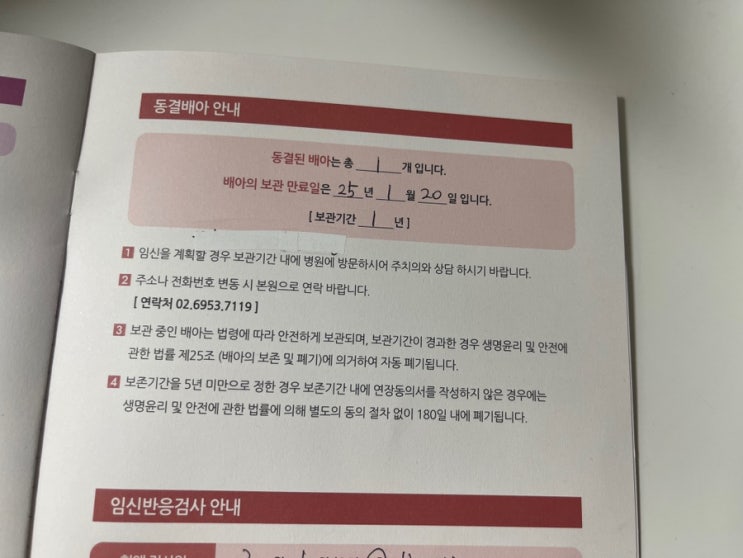

아기 심장소리도 듣고 했으니 카테고리를 임신일기로 변경해 보았다☺️ 내가 다녔던 난임병원 원장님께서...